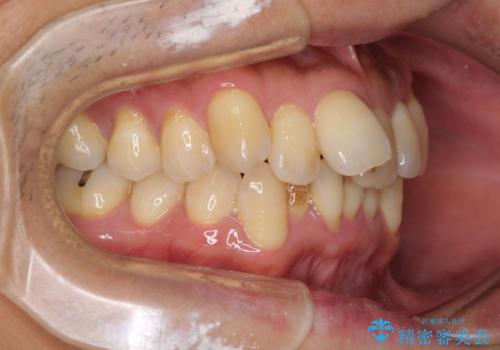

前歯のデコボコ ワイヤー装置での短期間治療

- 前歯のデコボコを気にして来院された患者様です。

インビザラインまたはワイヤー装置、どちらでも対応可能でしたが、自己管理の少なさ、期間の短さから、ワイヤー装置による矯正治療を行うこととしました。